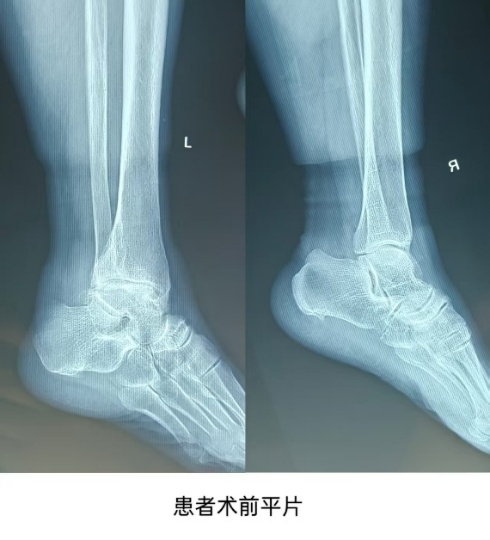

The patient, a 65-year-old female, had progressive pain in the left ankle for 5 years, which worsened with difficulty walking for 2 months. She came to our hospital for diagnosis, and after inquiring about her medical history, conducting a physical examination, and reviewing imaging data, she was diagnosed with “talar necrosis” and was admitted to the hospital. Considering the patient’s high activity demands, it was decided to perform a 3D printed guide-assisted total ankle joint replacement surgery. A multidisciplinary consultation was held with the radiology and surgical anesthesia departments, and after repeated communication with the prosthesis design engineer, the final surgical plan was confirmed and the surgery was conducted, lasting approximately 80 minutes. The patient has now been successfully discharged.